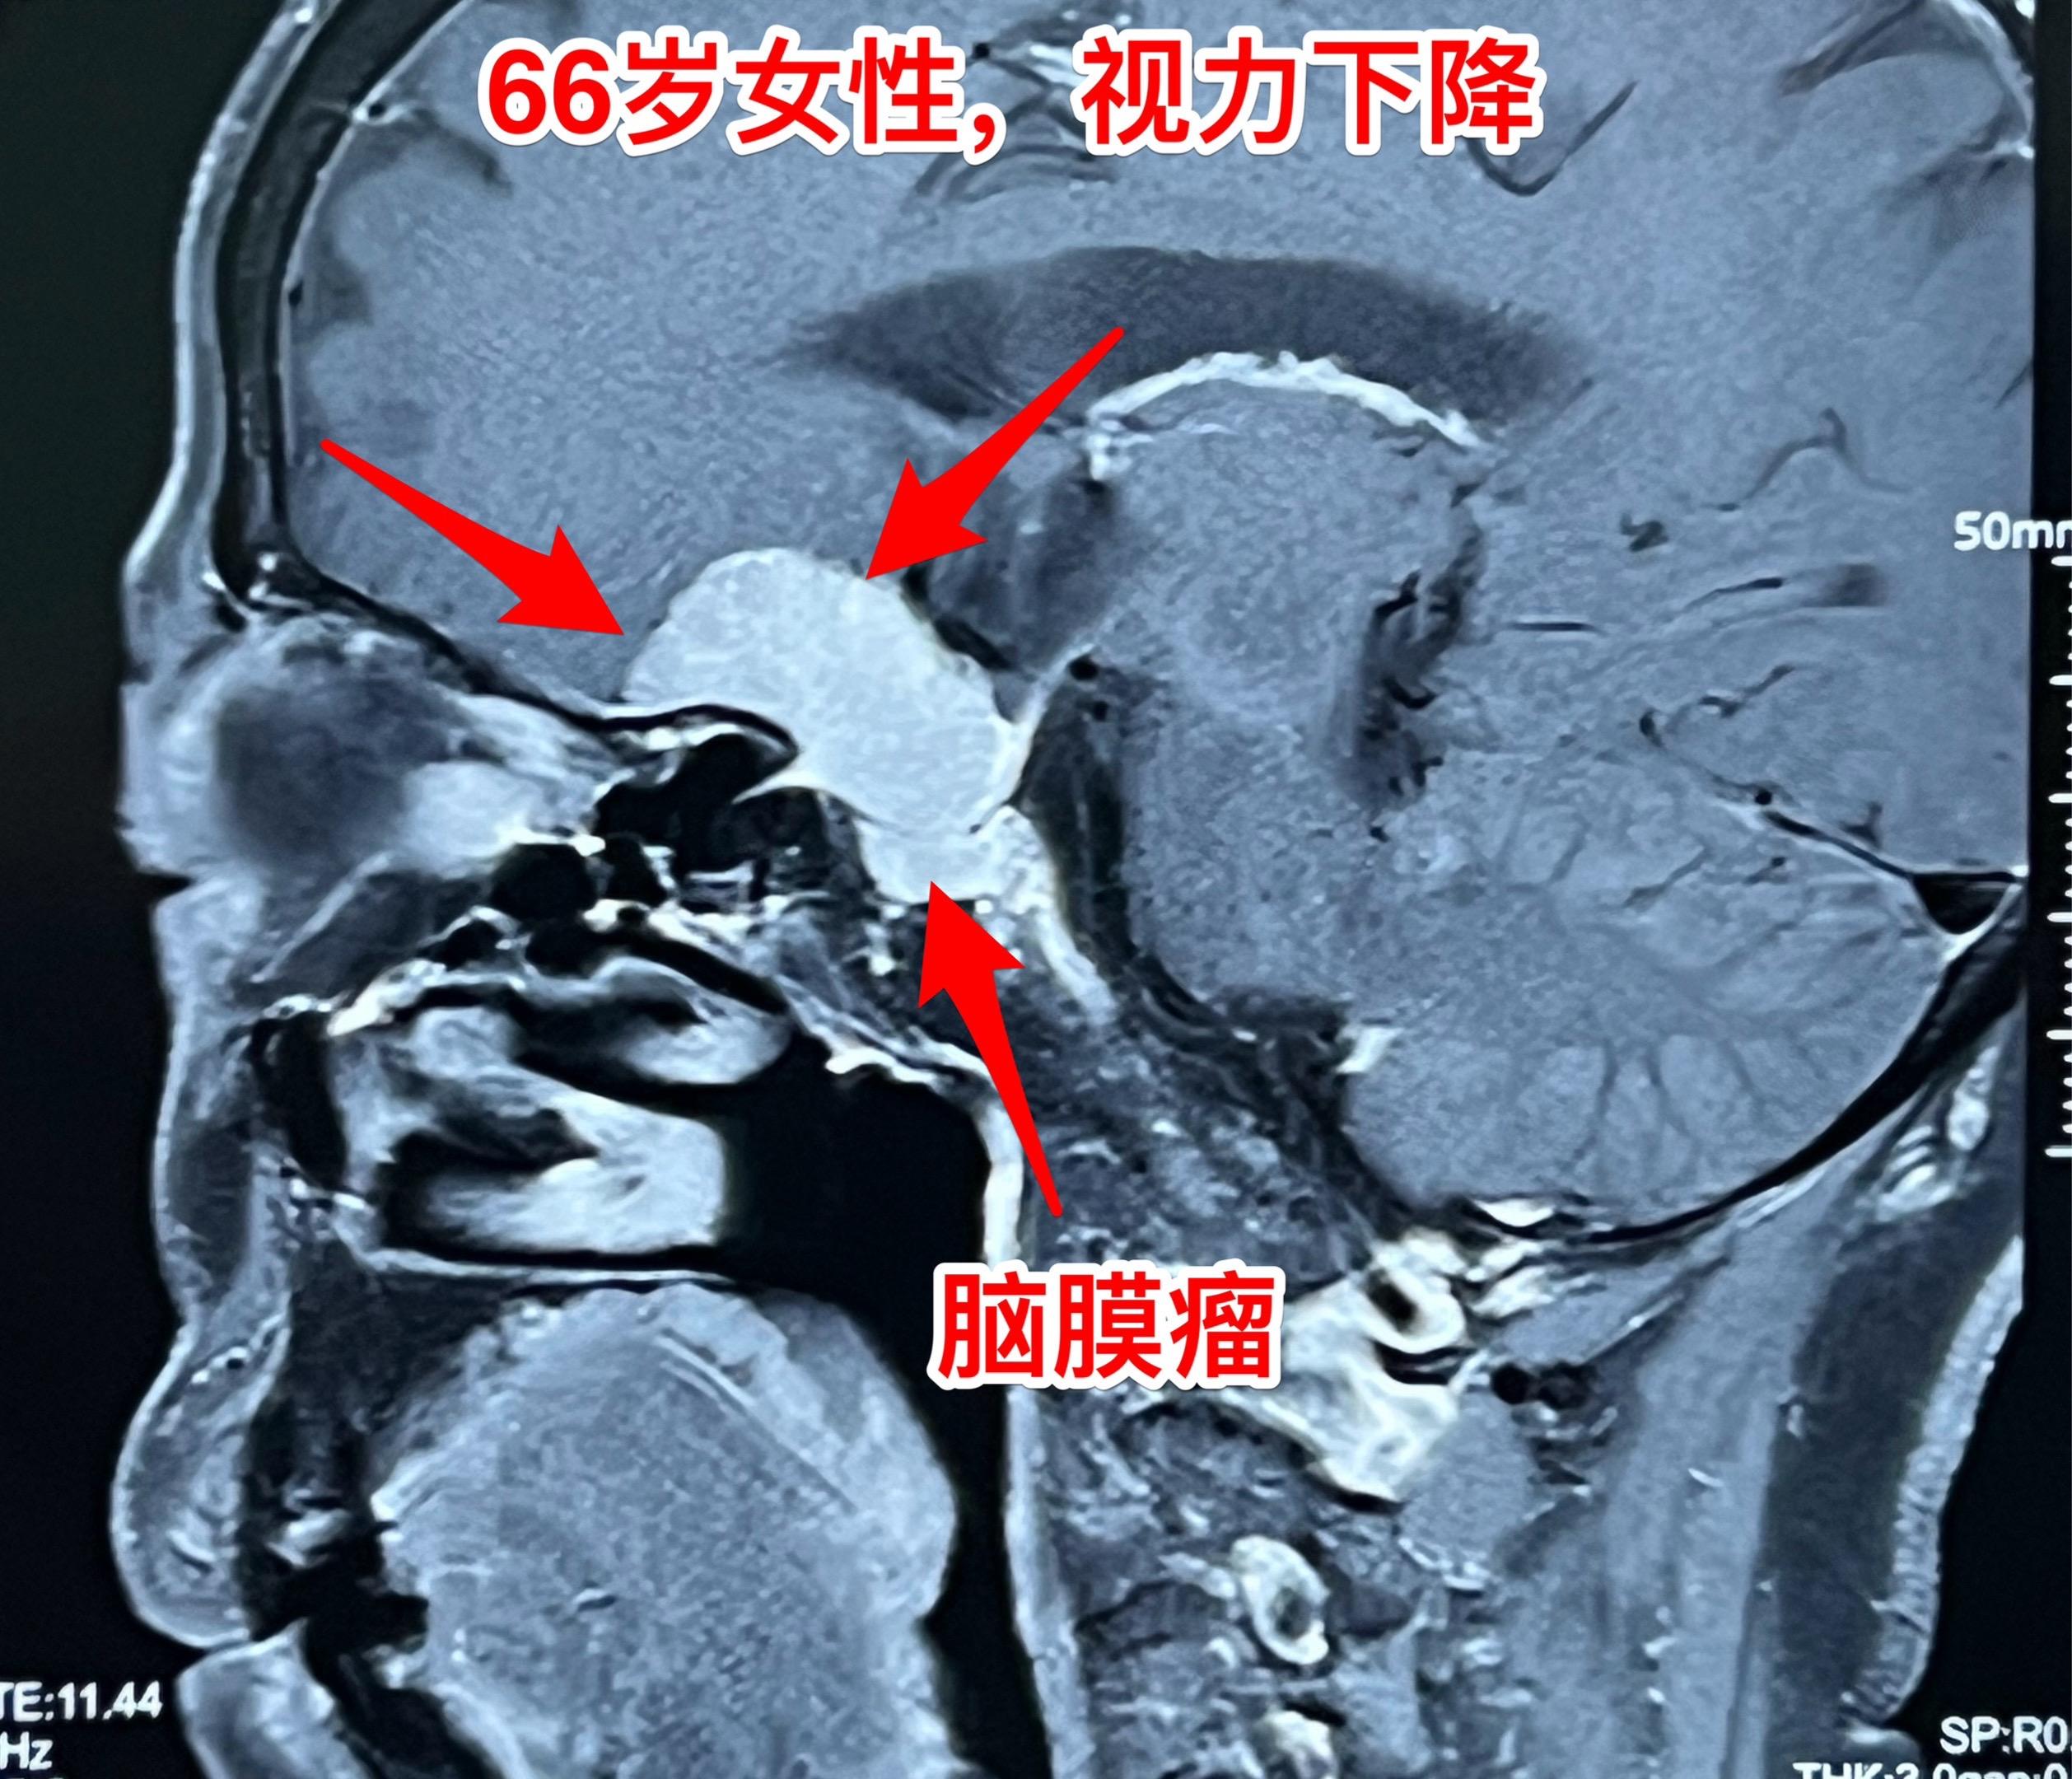

脑膜瘤也会造成视力下降。66岁吉林省女性,退休后喜欢开车到处旅游,并在旅游途中搞直播,拥有三十几万粉丝。 今年她感觉视力明显下降,开车有困难。作了磁共振发现鞍区脑膜瘤,见图。 脑膜瘤属于良性肿瘤,作手术切除肿瘤是最合适的治疗方法。9月16日作了开颅手术,将肿瘤完全切除。手术后病人感视力有改善。脑膜瘤视力下降